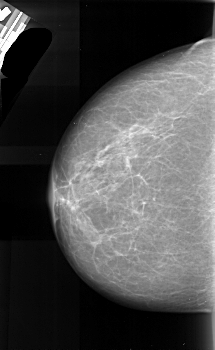

A_1040_1.RIGHT_MLO

RIGHT_CC LINES 5131 PIXELS_PER_LINE 2971 BITS_PER_PIXEL 16 RESOLUTION 42 NON_OVERLAY